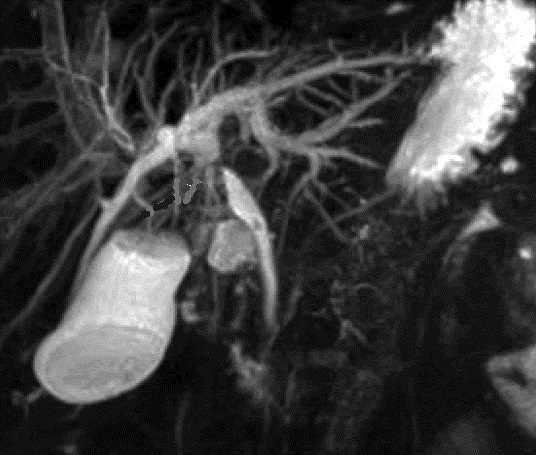

Image Cholagio-IRM et ERCP : C'est

image de calcul du vesicule biliaire en compressant au VBP

et image de dilatation du canal hepatique commun et des voies

biliaires intrahepatiques . La vesicule biliaire est enflame ,

frequemment distendu.avec imgage de calcul a infundibulum

.

Syndrome de Mirizzi type II , III :

Image d'une grand calcul a collet vesiculaire (

fleche rouge ) compressant au canal hepatique

commun . Sa portion superieur et voie biliaire intra

hepatique sont tres dilatees . Canal choledoque est

vue de moindre et non dilate ( Cholangio-IRM

recontruction en 3D ) |

Cholagio - IRM : Grand calcul a infundibulum

empreinte compressive au canal hepatique commun

. Vesicule biliaire est tres distendue . Voie

biliaire principale et voie biliaire intrahepatique

en amont leregement dilate ( syndrome de Mirizzi )

|

Une autre cas de syndrome de

Mirizzi type III . Cholagio - IRM du foie et

voie biliaire a recontruction en 3D . |